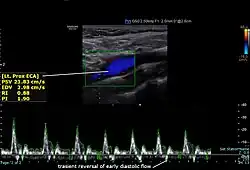

Left external carotid artery with normal spectral doppler ultrasound

The condition and health of the external carotid arteries is usually evaluated using Doppler ultrasound, CT angiogram or phase contrast magnetic resonance imaging (PC-MRI). Typically, blood flow velocities in the external carotid artery are measured as peak systolic velocity (PSV) and end diastolic velocity (EDV).[4]

PSV values greater than 200 cm/s are considered to be predictive of more than 50% of external carotid artery stenosis.[5]